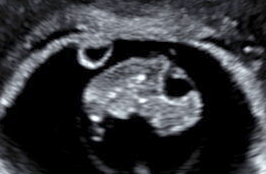

SoundView exists to serve the leadership and medical personnel of pregnancy medical centers. We specialize in limited obstetric ultrasound by providing didactic education, hands on training, and consultation. We equip those we train to serve their communities with integrity, compassion, and medical excellence.

Limited OB

Ultrasound

The initial training includes a required didactic component prior to the hand-on clinical education.